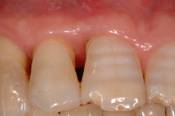

• PPD (periodontal pocket depth) [fig. 2];

•  Fig 2

Initial probing

Int J Med Sci Image